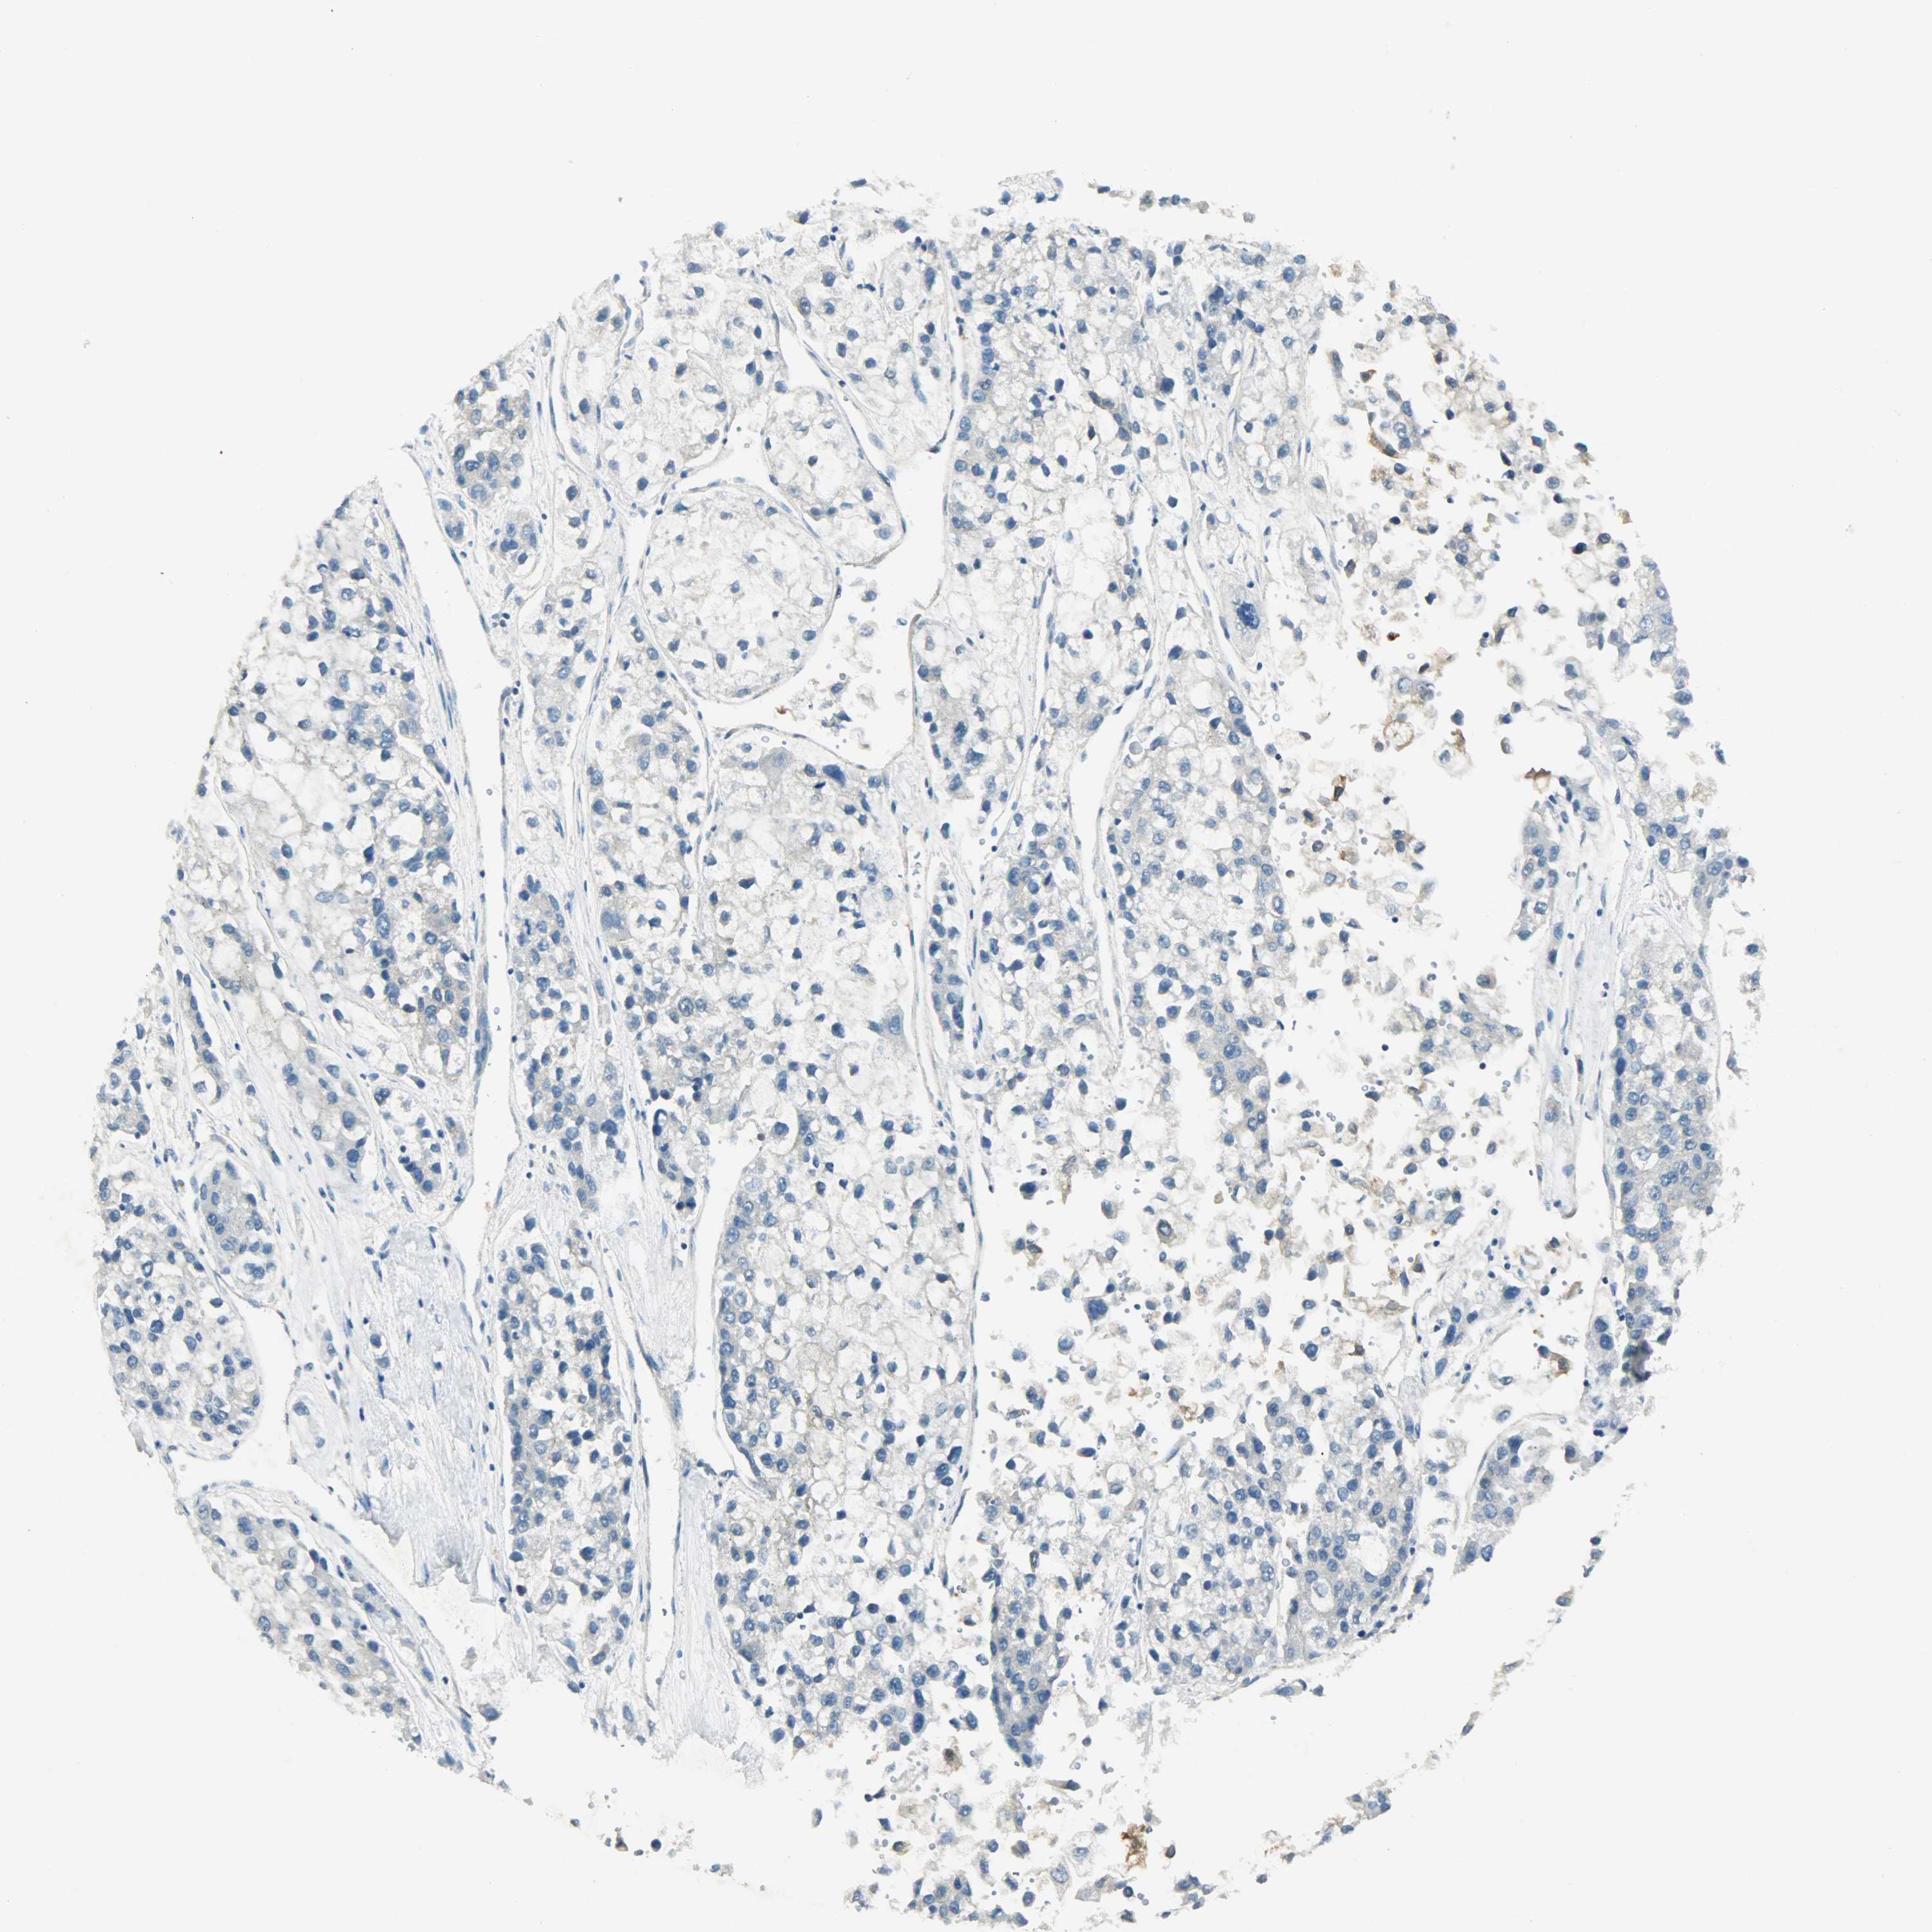

LIVER CANCER - Protein expressioni

A mouse-over function shows sample information and annotation data. Click on an image to view it in a full screen mode. Samples can be filtered based on level of antibody staining by selecting one or several of the following categories: high, medium, low and not detected. The assay and annotation is described here.

Note that samples used for immunohistochemistry by the Human Protein Atlas do not correspond to samples in the TCGA dataset.

Antibody stainingi

Antibody staining in the annotated cell types in the current human tissue is reported as not detected, low, medium, or high, based on conventional immunohistochemistry profiling in selected tissues. This score is based on the combination of the staining intensity and fraction of stained cells.

Each image is clickable and will lead to virtual microscopy that enables deeper exploration of all samples and also displays staining intensity scores, fraction scores and subcellular localization as well as patient and tissue information for each sample.

Antibody HPA004926

Staining

High

Medium

Low

Not detected

Intensity

Strong

Moderate

Weak

Negative

Quantity

>75%

75%-25%

<25%

None

Location

Nuclear

Cytoplasmic/membranous

Cytoplasmic/membranous,nuclear

Cholangiocarcinoma

Carcinoma, Hepatocellular, NOS